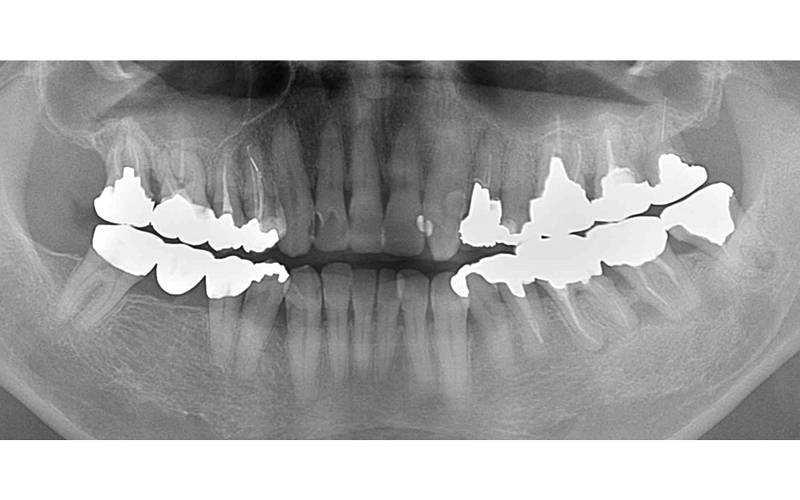

| 主訴 | 奥歯で噛めない・入れ歯が合わない |

|---|---|

| 年齢・性別 | 72歳・女性 |

| 治療期間・回数 | 10ヶ月(他の治療も同時進行) |

| 治療方法 | 骨造成・インプラント埋入 |

| 費用 | 合計:1,498,000円(骨造成を含む) |

| デメリット・注意点 | 自費診療のため費用がかかる。定期メンテナンスが必要。 |

| 備考 | 初診時、以前義歯を製作して貰ったみたいですが使用しておらず、奥歯で咬んでいない状態で来院。前歯が前方に出ているのが気になるとの事でした。 右上の端の歯は根の病変で保存不可能の状態でした。前歯の治療を含め奥歯にインプラント治療を選択しました。 |